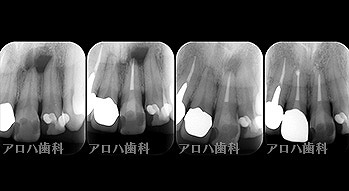

case5

左:頬側よりGP挿入。MB根尖の透過像と一致。

P根にも透過像。穿孔を疑う。

右:術後1年。

左:術前

右:術後1年

P根の穿孔封鎖

頬側の瘻孔